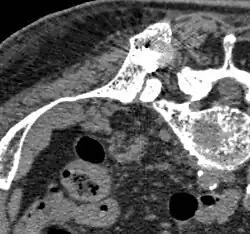

Scanner

La tomodensitométrie, ou tomographie axiale calculée par ordinateur est pratiquée le plus souvent après la radio X conventionnelle et la scintigraphie. Dans ces procédés d'imagerie, on détermine les domaines qui doivent être représentés par le scanner avec une résolution bien plus fine, et une meilleure qualité. Le scanner donne des informations sur la mesure de la destruction de l'os et la stabilité du domaine touché par les métastases osseuses[87]. Ces informations sont de grande importance pour la planification du traitement, en particulier pour des interventions chirurgicales éventuelles.

L'indication pour un examen au scanner est donc avant des interventions opératoires stabilisantes (par exemple une excision vertébrale), avant une biopsie (quand la lésion est visible en scintigraphie, mais pas en radio) ainsi que dans le cas de fractures menaçantes ou déjà survenues[87].

- TEP/scanner à la choline 18F

Métastases ostéolytiques dans la deuxième vertèbre du cou (Axis) d'un cancer de la prostate.

Métastase ostéocondensante d'un cancer de la prostate dans la hanche

Scanner d'une métastase d'un cancer de la prostate à gauche dans le pubis (à dr. sur l'image)

TEP de la même métastase au pubis

Image composite scanner/TEP de la même métastase